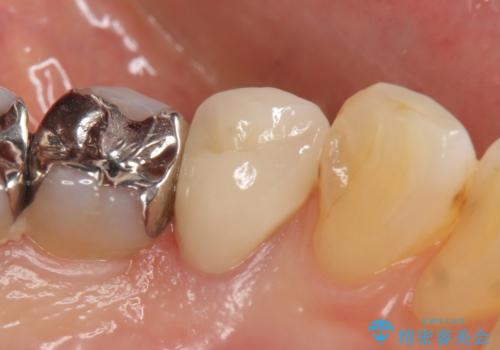

オールセラミッククラウン 疼きの治まらない歯の治療

- 他院にて左下4の根管治療を行っていたが、疼くような痛みが引かないため当院にいらっしゃった方の症例です。

左下4の再根管治療を行い症状が治まったのち、オールセラミッククラウンによる補綴を行いました。

今回用いたオールセラミッククラウンはジルコニアフレームという白い素材の上にセラミックを盛っているため、審美性が非常に高いのが特徴です。

また、ジルコニアは人工ダイヤモンドの材料にも使われているほど高い強度を持っており、そのためオールセラミッククラウンは審美性だけでなく、奥歯やブリッジの補綴も可能とするクラウンです。